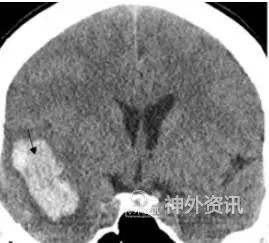

图26为一例右侧破裂大脑中动脉瘤伴颞叶血肿,根据定位及CTA看血肿及破裂处如图27、28、29,如果从绿色箭头路径(图28),不仅动脉瘤颈可能会部分遮挡,且在分离时极可能先出现动脉瘤破裂,而从黄色箭头路径(图29),则不仅夹闭无遮挡,且不会先接触破裂点,造成术中破裂。

图26. 右侧大脑中破裂伴颞叶血肿。

图27. 右侧破裂大脑中动脉瘤(绿色箭头路径侧裂开口更靠近前床突方向,黄色箭头路径侧裂开口更靠近后方)。

图28. 绿色箭头路径模拟,瘤颈部分遮挡,分离时容易在未临时阻断情况,先触碰动脉瘤破裂点。

图29. 黄色箭头路径模拟,可先暴露载瘤动脉并予以临时阻断,然后分离瘤颈夹闭,瘤颈无遮挡,同时减少在临时阻断和最终夹闭前对动脉瘤破裂点的骚扰。